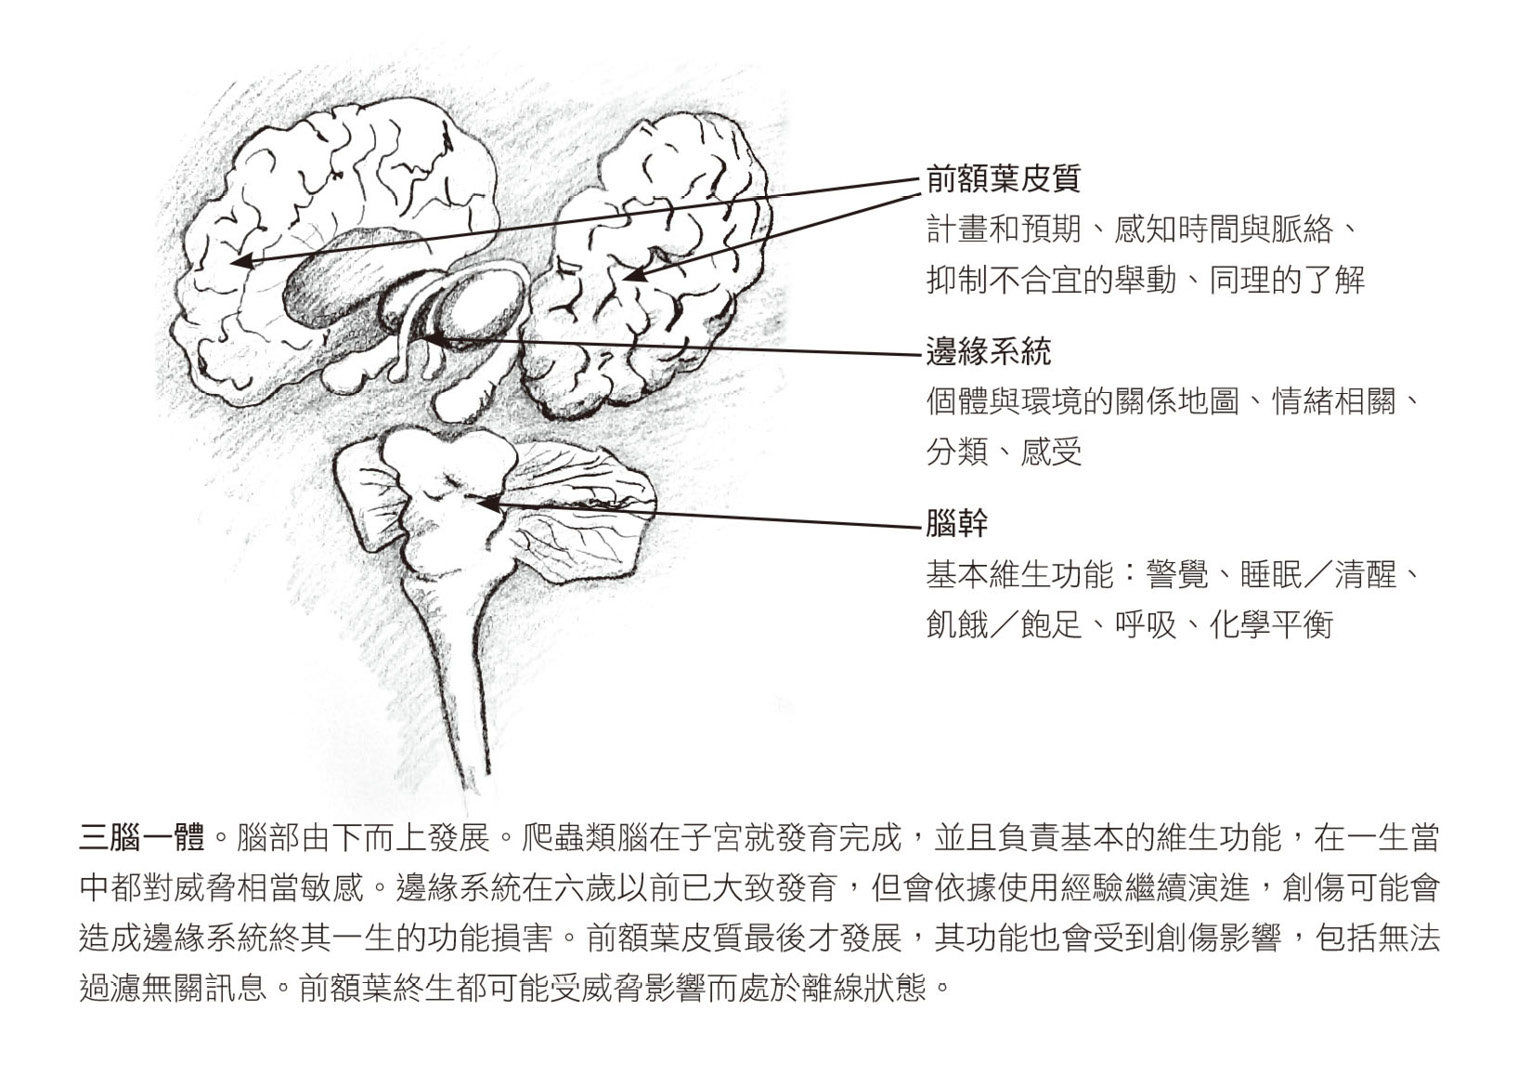

上一頁的圖說明瞭整個身體面對威脅時的反應。

● 由下而上的大腦

大腦最重要的工作,是確保我們即使在最險惡的情境下也能存活,其他則是次要。為了達成這項任務,大腦需要:一.產生內在訊號,提醒我們身體的需求,例如食物、休息、被保護、性,以及安身避難。二.製作一份地圖,指引我們何處能滿足這些需求。三.產生必要的能量和行動,讓我們抵達能滿足需求的地方。四.提醒我們沿途的危險和機會。五.根據當下情境的需要調整行動。4人類是哺乳類動物,只有在群體中才能生存、茁壯,因此上述所有大腦原則都必須透過協調與合作才能達成。出現心理問題,表示內在訊號無法正常運作、地圖無法指引我們前往應去的地方、我們因過於驚嚇而動彈不得、採取的行動與需求不一致,或是人際關係破裂。接下來,文章會探討的每個腦部結構都在這些基本功能中扮演某個角色,你也將看到,創傷如何影響當中的每個結構。

人類的理性、認知腦其實是大腦中最年輕的一區,只佔顱內大約三十%的區域。理性腦主要關注外在世界,包括理解人類和事物的運作、設法達成目標、管理時間、規劃行動。理性腦下方是兩個在演化史上更古老且某種程度上相互獨立的腦,負責所有其他功能:隨時記錄並管理生理機能,以及辨識舒適、安全、威脅、飢餓、疲憊、慾望、渴求、興奮、愉悅和痛苦。

大腦是由下而上建造的,胎兒在子宮時,大腦一層一層地發展,如同演化的過程一樣。最原始的腦在我們出生時已經上線運作,那是我們古老的動物腦,通常稱為爬蟲類腦,位於腦幹,也就是脊髓進入顱骨處的上方。這個爬蟲類腦負責新生嬰兒能做的每件事:吃、睡眠、清醒、哭泣和呼吸,以及感覺溫度、飢餓、潮濕和疼痛,還有排尿和排便以清除體內毒素。腦幹和其正上方的下視丘共同控制身體的能量水平,協調心肺功能、內分泌系統和免疫系統,確保這些基本的維生系統都能維持相對穩定的內部平衡,也就是恆定狀態。

呼吸、進食、睡眠與排洩都是如此基本的功能,以至於我們在探究複雜的心智與行為時,很容易就忽略了這些功能的重要性。然而,如果你有睡眠困擾或胃腸不適,總是覺得飢餓,或一被人碰觸就想大叫(常見於受創的兒童和成人),你的整個生命體就是處於失衡狀態。令人詫異的是,許多心理問題都涉及睡眠、食慾、碰觸、消化和警覺等方面的障礙。任何有效治療創傷的方法,都必須處理這些身體基本的內部管理功能。

爬蟲類腦的正上方就是邊緣系統,又稱為哺乳類腦,所有群居並哺育幼兒的動物都有。這一區的腦是情緒的所在地、危險的監測器、愉快或驚嚇的評判員,也是判斷何者攸關生存的裁決者,要到嬰兒出生後才真正開始發展。它也是中央指揮所,幫助我們因應在複雜社會網絡中生存的種種挑戰。

邊緣系統一方面受嬰兒對經驗的反應所形塑,二方面會和嬰兒的基因組成及出生時的氣質結合。(有兩個以上小孩的父母很快就會發現,對於同類事件,每個小孩從一出生就有不同的反應強度和反應方式。)嬰兒在發展該區大腦的過程中,所有經歷都會成為情緒與知覺地圖的一部分。正如我的同事布魯斯.佩裡的解釋,大腦是透過「使用」而發展5,這是神經可塑性的另一種描述方式,這個新近的發現指出一起活化的神經元會連結在一起,形成新的迴路。某個迴路若是一再被活化,就會變成一種預設狀態,即最可能出現的反應。如果你感到安全與被愛,你的大腦會擅長探索、遊戲和合作;如果你感到害怕與不被需要,大腦就會專門處理害怕和被遺棄的感受。

在襁褓和學步期,我們透過移動、抓取、爬行,以及發現哭、笑或抗拒的後果來學習認識世界。我們持續拿周遭環境來實驗:我們和外在的互動會如何改變身體的感受?如果你去參加兩歲幼童的慶生會,你會注意到這個小寶貝不使用語言就能跟你打交道、逗你玩、對你擠眉弄眼。這些早期的探索,會影響負責處理情緒與記憶的邊緣系統的發展,但這些大腦結構也可能因為後來的經驗而被大幅修改,例如因為親密的友誼或美麗的初戀而變得更好,或因為暴力攻擊、殘酷的霸凌或忽視而變糟。

本書中所說的「情緒腦」,就是爬蟲類腦加上邊緣系統。6情緒腦位於中樞神經系統的中央,關鍵任務是照料你的健康安樂,當情緒腦偵測到危險或一些特殊機會(例如可能的伴侶),會釋放大量荷爾蒙來提醒你,這會產生一些內臟感覺(從輕微噁心到胸口緊繃都有可能),影響你的注意力,讓你在生理或心理上採取不同的行動。就算是最輕微的程度,這些感覺也會對我們生活中大大小小的決定產生巨大的影響,包括選擇吃什麼、想在哪裡睡覺以及跟誰睡在一起、偏愛哪種音樂、想做園藝還是在合唱團唱歌、跟誰交朋友,或討厭誰。

情緒腦的細胞組織和生物化學比新皮質(理性腦)單純,也以較為全面的方式來評估輸入的訊息,根據粗略的相似性快速做結論,(教科書上的例子是,你一看到蛇會先害怕而後退,後來才發現那只是一條繩子。)而理性腦的設計則是爬梳整理複雜的選項。情緒腦會啟動預設好的脫逃計畫,例如戰或逃反應,這些肌肉與生理反應都是自動的,無需我們的思考或計畫就能運轉,而意識和理性功能通常是在威脅結束之後才會趕上。

最後是大腦的最頂層:新皮質,人腦和其他哺乳類動物都有這一層大腦,但人類的新皮質要厚上許多。構成大部分新皮質的額葉會從兩歲開始快速發展。古代哲學家說七歲是「理性之年」,我們也認為小學一年級是未來的序曲,此時的發展便與額葉功能有關:能安靜坐好、控制括約肌、使用語言而非直接行動、理解抽象與象徵概念、計畫明天的事情,或與師長同學和睦相處。

額葉負責的功能7使我們在動物界獨一無二,讓我們能夠使用語言和抽象思考,能夠吸收和整合大量資訊並賦予意義。黑猩猩和恆河猴的語言能力雖令我們興奮,但只有人類能運用文字和符號,並由此創造出共有的、精神性的和歷史性的脈絡,形塑我們的生活。

額葉使我們能夠計畫與反思,想像及推演未來的情景,幫助我們預測某個行為(應徵一個新工作)或忽略某件事(不付房租)的後果,好讓我們能抉擇。額葉還是驚人創意的基礎。歷世歷代的人運用額葉,在密切合作下創造出文化,讓我們從獨木舟、馬車與書信的年代,來到噴射機、汽車與電子郵件的時代。額葉也給了我們諾姆畫的救命彈簧墊。